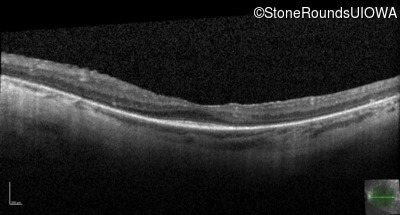

Optical Coherence Tomography - Left - 20/50 -2

Exemplar / OCT Stack

OCT Stack